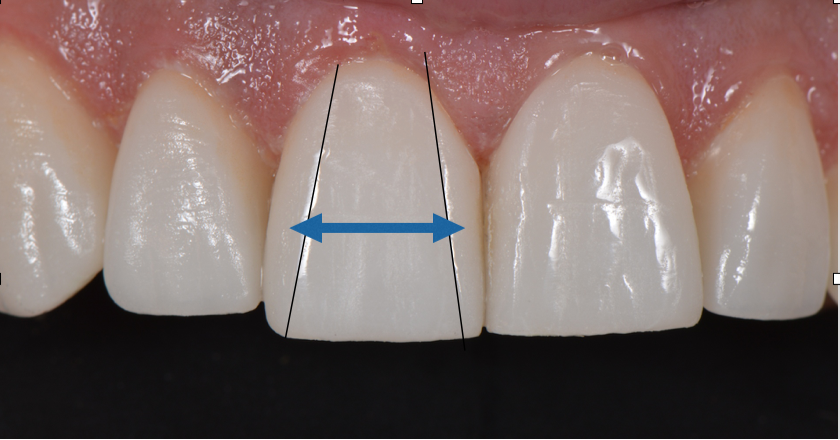

He had a low lip line, some dentoalveolar extrusion of the lower anteriors and a deep bite. His maxilla was retrognathic and he could have had orthognathic surgery to improve the position of his maxilla, but he declined. Instead, we restored his upper 10 teeth with IPS e.max restorations, equilibrated to function. We could not add much length, but we did improve the dominance of his centrals with more space between the line angles creating more reflective surface.

Line angles marked in pencil on porcelain.

Final restorations with improved dominance created by a higher value and increased light reflective surface.

Increased light reflective surface aided by the line angles or the heights of contour of the central incisors being further apart.

Final result is a more dominant smile for the patient.